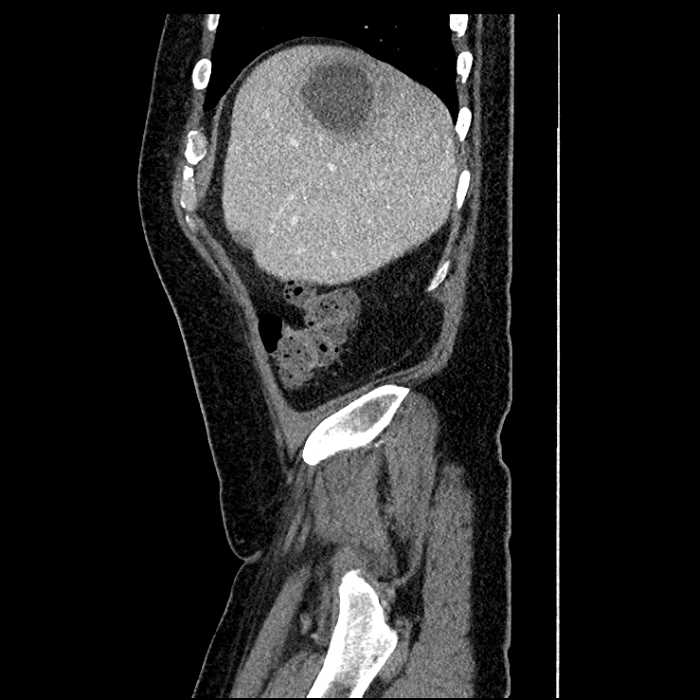

Age: 63

Sex: Male

Indication: Abdominal pain

• Large fluid density structure in hepatic segments 7 and 8 measuring 10 x 7 x 7 cm with internal septation and circumferential ill-defined low density compatible with edema

• Hepatic abscess

Acute sigmoid diverticulitis complicated by a small contained perforation and a large abscess in the right hepatic lobe. Additional small subcapsular abscesses along the anterior margin of the left hepatic lobe.

• The classic CT imaging appearance is a double target sign with internal low density surrounded by an internal enhancing rim (capsule) and a low density external rim (edema)

Hepatic abscess showing the double target sign with low density internally surrounded by a thin inner enhancing rim (red arrow) and ill-defined outer low density rim (yellow arrow). Blue arrow indicates an internal septation. Red arrows: additional smaller subcapsular abscesses. Red arrow: focal contained perforation associated with diverticulitis.